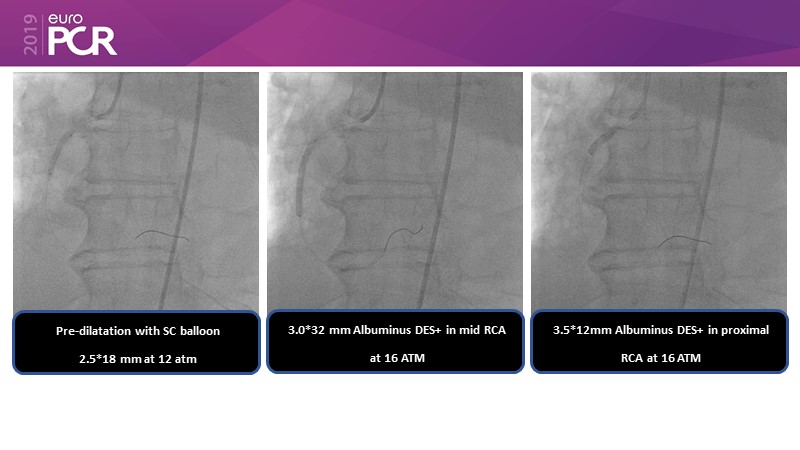

Consult this session to get insights about the need for a dedicated drug eluting stent (DES), as well as the benefits of a DES+DCB strategy, for diabetes mellitus (DM) and acute MI (AMI) patients.

- To understand and discuss the need for a dedicated DES for diabetes mellitus (DM) and acute MI (AMI) patients

- To understand and learn benefits of DES+DCB strategy to provide uniform and homogenous drug delivery in patients with diabetes mellitus and acute MI